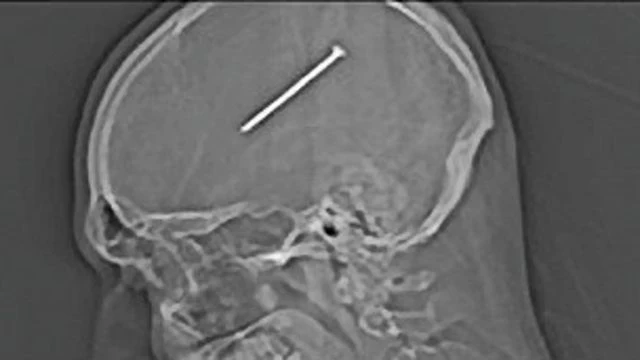

بعد وصوله إلى مستشفى Sultanah Bahiyah في ألور ستار، كانت عين الرجل تنزف وتتورم، وأدى الحادث إلى إصابته بفقدان مؤقت للبصر. تم إعطاؤه لقاح الكزاز والمضادات الحيوية بشكل فوري، وقد أظهرت الأشعة السينية والأشعة المقطعية وجود المسمار المخترق في الفص الأمامي للدماغ.

المسعفون نجحوا في إزالة المسمار والأنسجة التالفة، ورغم نجاح الجراحة، فإن الرجل لا يستطيع إغلاق عينه بشكل صحيح، وفقد القدرة على رؤية الضوء من خلال عينه المصابة.